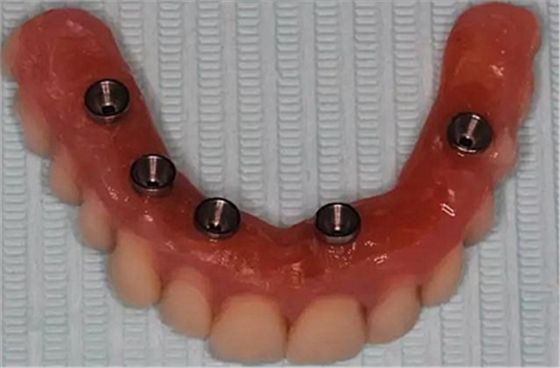

牙列缺失患者由于支持、固位、穩(wěn)定不足導(dǎo)致義齒效果差,如果在牙槽嵴內(nèi)植入種植體,種植體可以根據(jù)種植體數(shù)量不同提供義齒不同程度的固位、穩(wěn)定、支持,獲得不同的修復(fù)效果。當(dāng)單頜牙列缺失患者使用1-2顆植體,植體和覆蓋義齒之間可以靠一些附著體如磁性附著體、桿卡式附著體、球帽式附著體等裝置連接,主要提供固位和穩(wěn)定作用,少量的支持作用,當(dāng)單頜牙列缺失使用4顆植體時,很大部分支持力可以由植體承擔(dān),當(dāng)使用4顆以上植體時可完全由種植體提供義齒的支持、固位和穩(wěn)定,甚至制作為不可摘戴的全口固定種植義齒。